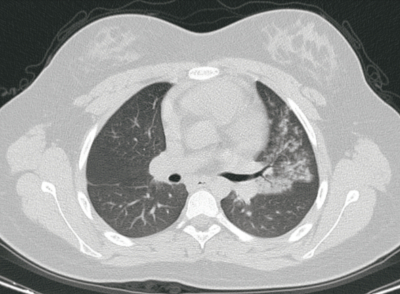

血液所見:赤血球 508万、Hb 14.3 g/dL、Ht 41 %、白血球 5,300(好中球 45 %、好酸球 2 %、好塩基球 1 %、単球 10 %、リンパ球 42 %)、血小板 30万。血液生化学所見:AST 22 U/L、ALT 24 U/L、LD 238 U/L(基準 120-245)。CRP 3.6 mg/dL。新型コロナウイルス〈SARS-CoV-2〉PCR検査は陰性であった。胸部エックス線写真及び肺野条件の胸部CTを別に示す。